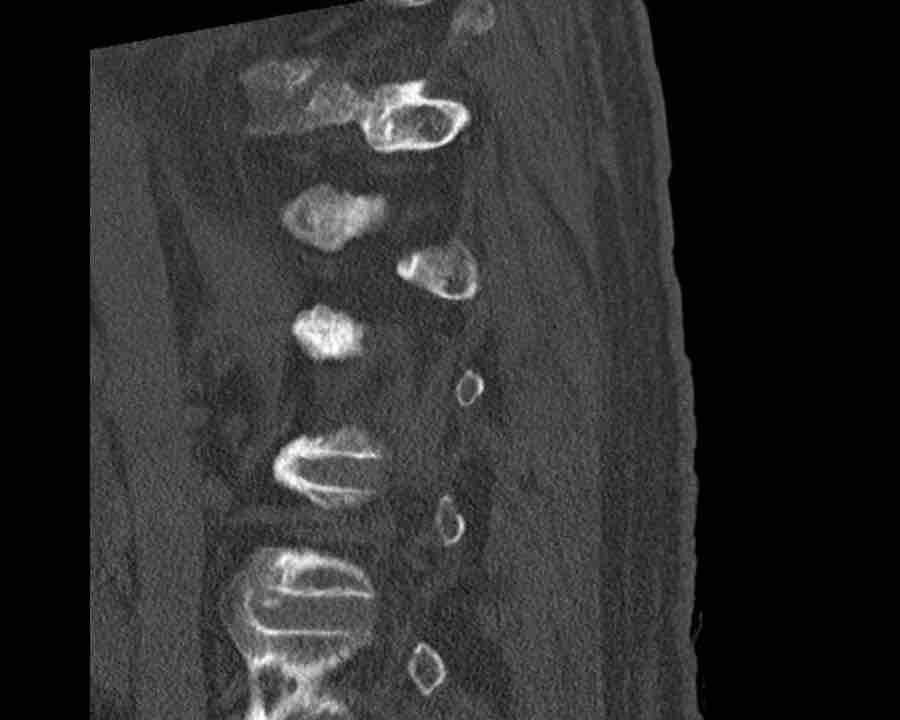

Scroll through the images.

What is the highest AO-type of injury?

Any additional findings?

Then continue with the next images…

Findings

- Black arrows: horizontal fractures through the pedicles as a result of flexion distraction trauma.

- White arrows: soft tissue swelling indicating injury to posterior ligaments.

- Circle: compression fracture of posterior wall (2 points) and two endplates (2 points)

Conclusion

Type B2-A4

Flexion distraction injury with separation on the posterior side and a secondary burst fracture involving both endplates and the posterior wall.